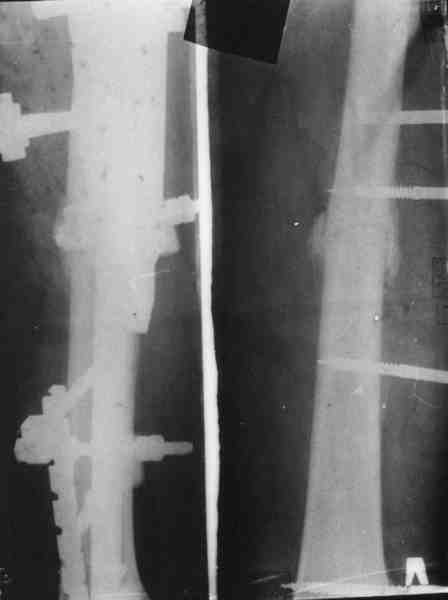

Вот еще информация, ознакамливайтесь pls/

С ув. Сергей Мелашенко,

Приморск, Запорожская обл.

Ukraine